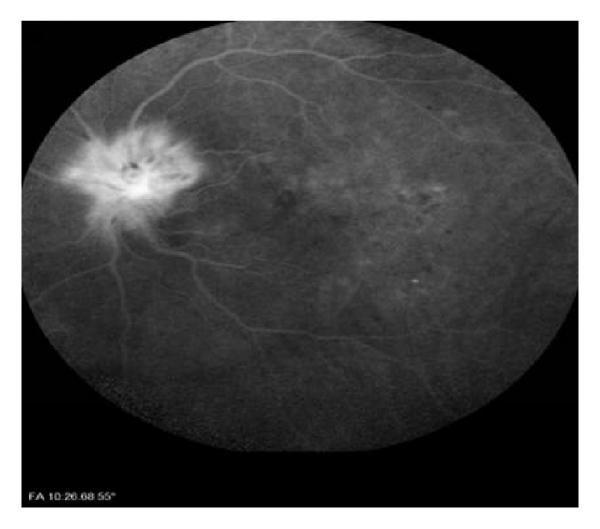

He returned to the eye clinic with a sudden painless visual loss in his left eye of two days’ duration in October 2014. On our examination, left afferent pupillary defect was present. Color vision was 7/21 in OD and 1/21 in OS with Ishihara pseudoisochromatic plates. Visual acuity was 8/10 in OD and 1/10 in OS. Slit-lamp examination was unremarkable OU. Intraocular pressure was within normal limit bilaterally. While right optic disc had only drusen and no physiologic cup, left optic disc also was hyperemic and segmentally swollen and a peripapillary splinter haemorrhage was present (Figure 2(a)). The laboratory tests, including complete blood count, erythrocyte sedimentation rate, and CRP, were normal. There was prominent fluorescein leakage at the left optic disc (Figure 2(b)). OCT disclosed mild subretinal fluid in OS (Figure 2(c)) and no abnormality in OD. Visual field testing disclosed inferior altitudinal scotoma in OD most possibly in association with disc drusen and severe diffuse depression in OS (Figure 2(d)).

(a)

(b)

(c)

(d)